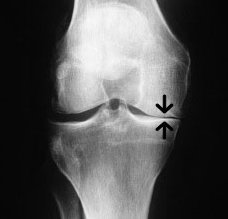

A good history and examination will highlight any issue with the cruciate and collateral ligaments and the menisci. X-rays may show any narrowing of the joint space due to meniscus problems and cartilage loss and those will further add to the overall assessment.